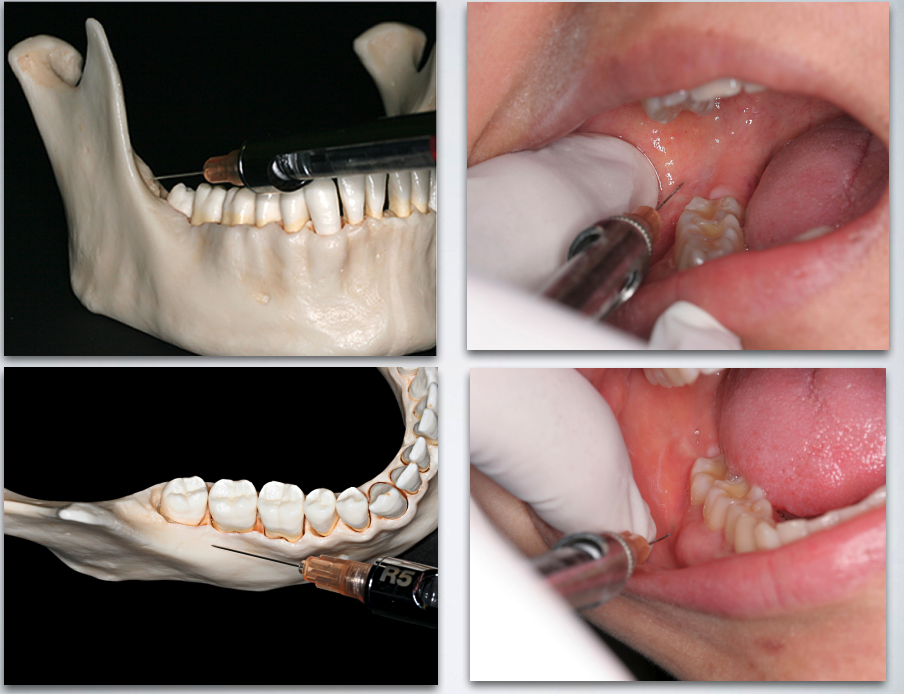

target areas for which technqieu?

AKINOSI CLOSED MOUTH TECHNIQUE

what is the proper height of insertion with AKINOSI CLOSED MOUTH TECHNIQUE?

mucogingival junction of maxillary 2nd or 3rd molar

what is the proper insertion depth with AKINOSI CLOSED MOUTH TECHNIQUE?

25 mm (measured from maxillary tuberosity)